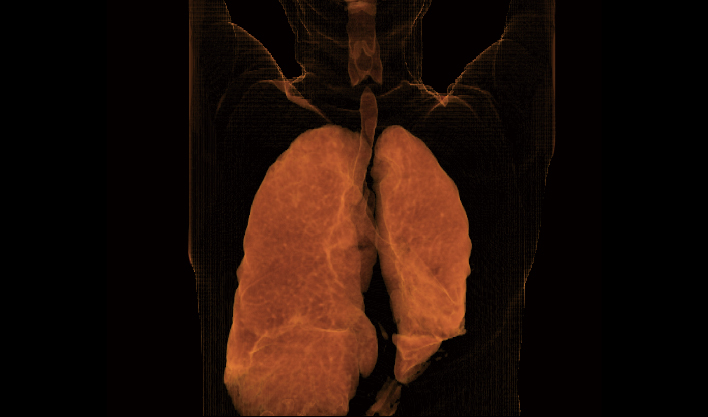

El detector de área amplia, combinado con la rotación de alta velocidad, garantiza imágenes de alta resolución y minimiza los artefactos de movimiento.

Captura instantánea para evitar artefactos por movimiento respiratorio, lo que mejora la tasa de éxito de los exámenes.